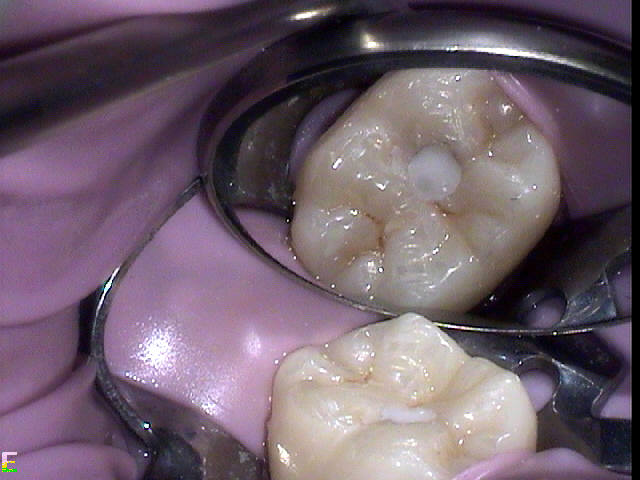

Excellent diagnosis essentially begins with two fundamental components: a doctor willing to listen to the patient’s chief complaint, and proper diagnostic tools. Among the most important tools are a precise periapical radiograph (PA) and bitewing (BW). Although a PA is often enough to provide an accurate portrayal of the patient’s condition, sometimes it alone does not suffice. Figure 1, Figure 2, and Figure 3 demonstrate a case that illustrates this point clearly. Despite two acceptable PAs (Figure 1 and Figure 2), it is difficult to assess the source of the patient’s pain to temperature. However, the BW radiograph Figure 3 provides significantly more clarity than either of the two PAs. The BW depicts localized bone loss (around tooth No. 2), a pulp stone (No. 2), a flat occlusion, numerous calcified canals, multiple restorations in tooth No. 30, and gross decay especially on tooth No. 3, which is the source of the patient’s pain to temperature. In this instance these images depict how much more useful a BW can be than just a conventional PA.

Figure 4 through Figure 10 depict several teeth that have conservative accesses while still allowing the clinician to adequately instrument and clean each tooth to achieve effective root canal therapy. The success of these cases still hinges on the proper cleaning and shaping of the root canal system, and while conservative accesses are desirable, too small of an access can lead to missed canals, poor instrumentation, improper cleaning, and, ultimately, a failed procedure.